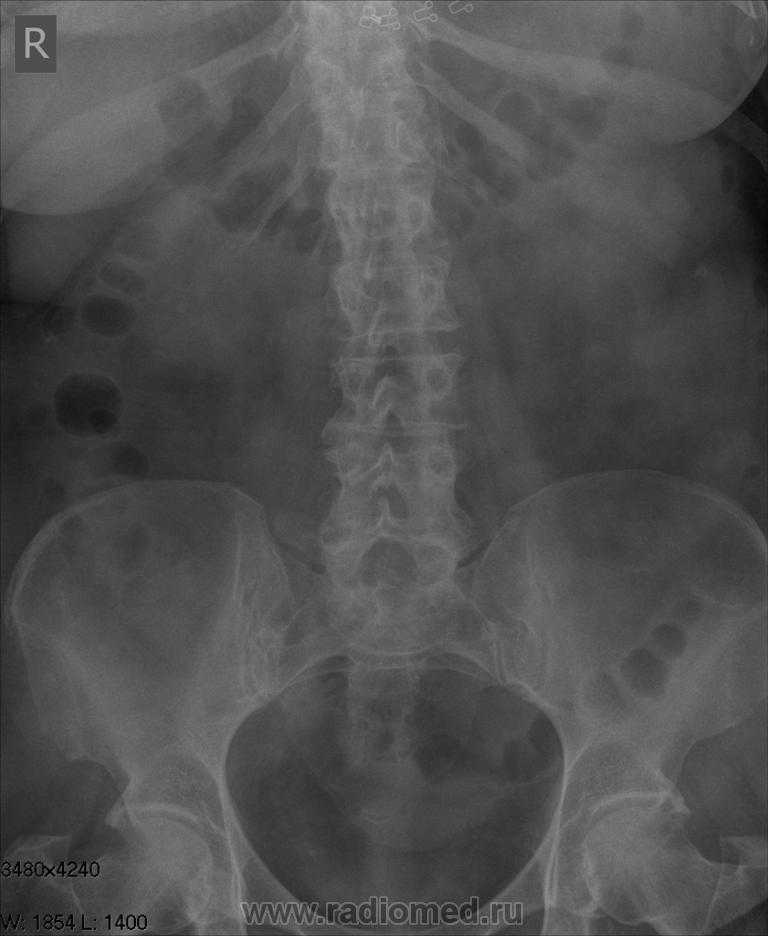

Медицинские изображения и примеры эксреторной цистографии